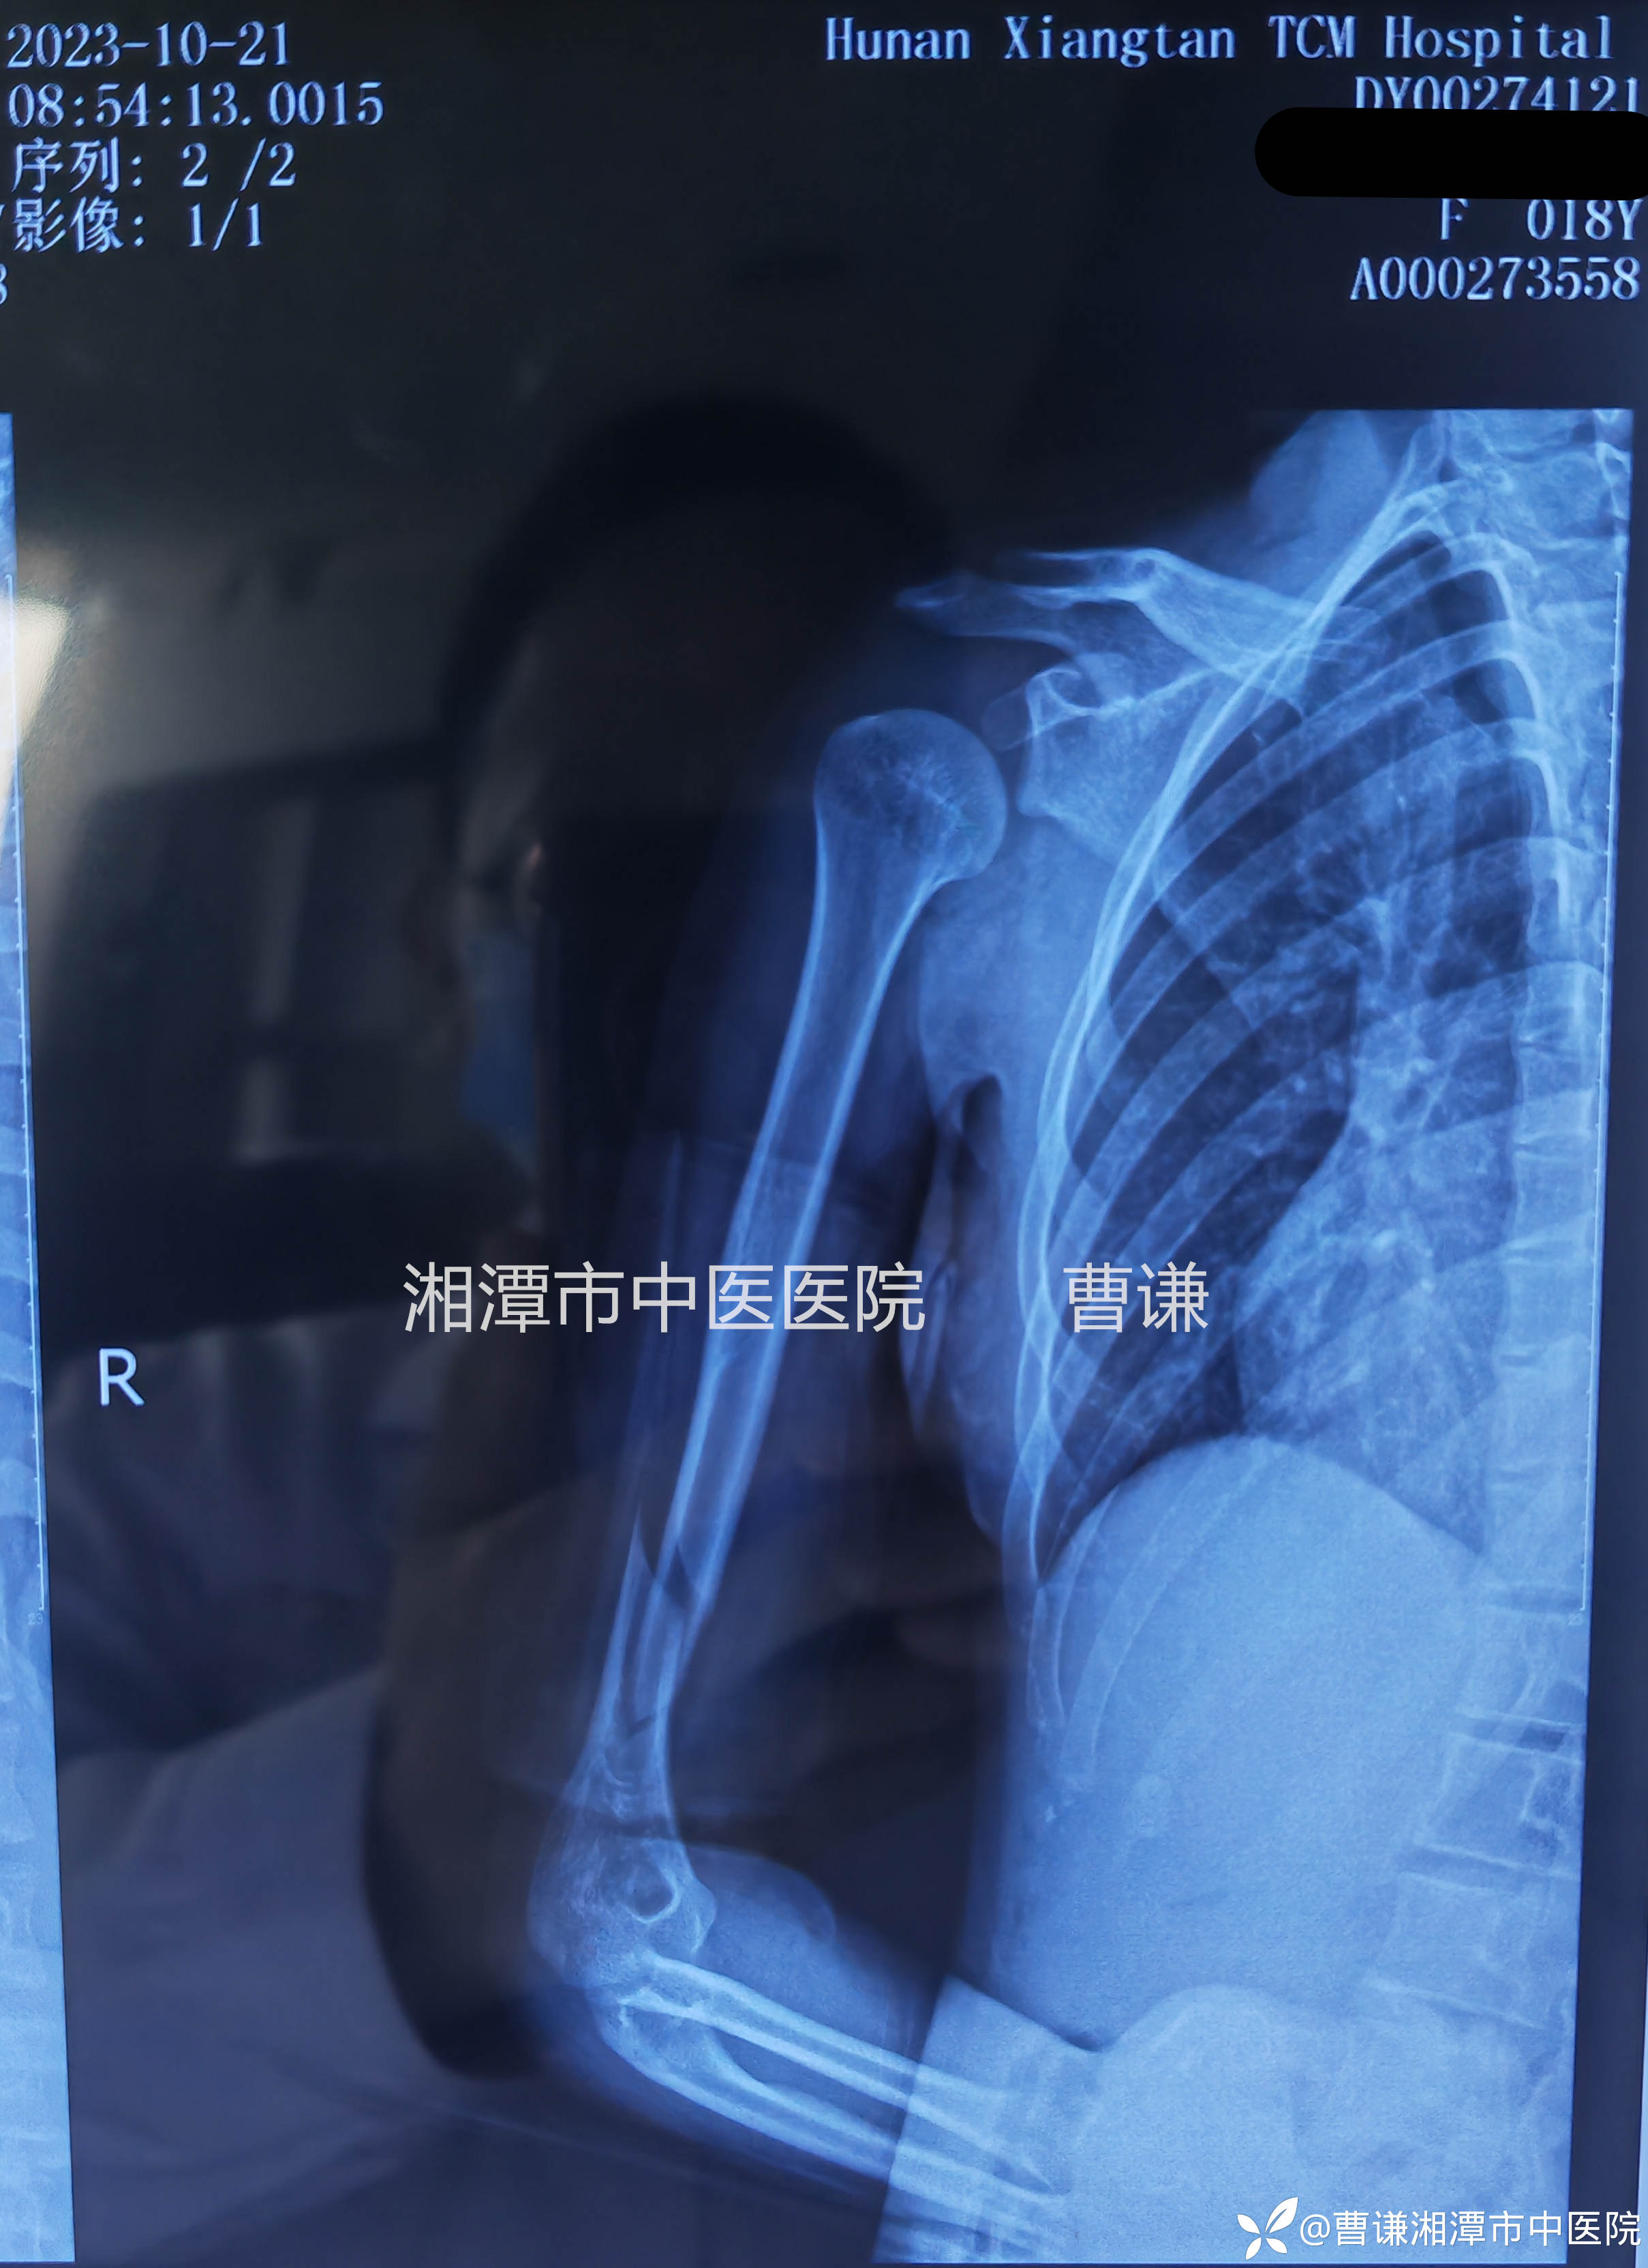

伤后17天拍片复查示骨折对位对线情况同前,肩关节有半脱位改变,开始带着夹板被动活动患肢,包括肩关节前屈、外展及环转,肘关节屈伸活动。